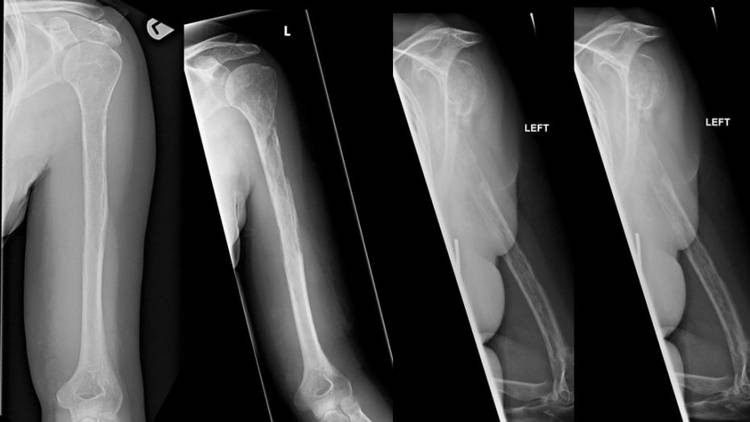

Trong trường hợp của người phụ nữ 44 tuổi tại bệnh viện Hoàng gia Edinburgh, cô đến khám và phàn nàn về cơn đau bất thường ở vai trái. Chụp X-quang cho thấy có tổn thương trên xương của cô. Mới đầu các bác sĩ tưởng đó là dấu hiệu ung thư rõ ràng thế nhưng kết quả sinh thiết lại chứng minh phán đoán này không chính xác.

Trong hơn một năm tiếp theo, các triệu chứng đau của bệnh nhân lại càng trầm trọng. Cô bị đau, sưng ở cánh tay, va đập nhẹ cũng có thể khiến xương bị gãy đầy đau đớn. Thế nhưng các bác sĩ vẫn không có kết luận chính xác.

Cuối cùng, sau 18 tháng ròng, các bác sĩ cũng có câu trả lời. Bằng cách quan sát các ảnh chụp X-quang, bác sĩ nhận thấy cấu trúc xương trong cơ thể người phụ nữ mờ dần sau mỗi lần tái khám. Nhiều xét nghiệm được tiến hành và cũng xác nhận rằng xương của bệnh nhân biến mất theo nghĩa đen. Tuy nhiên, các mạch máu lại tăng trưởng thay thế cho mô xương của cô.